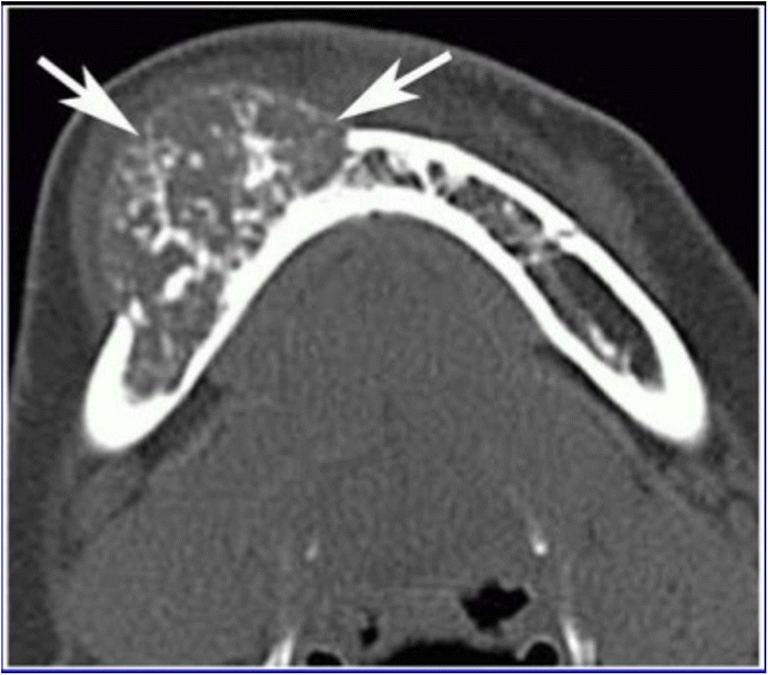

A 56-year-old female with multiple comorbidities presented with a swelling in the lower jaw (Figs. 1 and 2). On examination, it was a hard 6 × 5 cm swelling in the right mandible, 3 cm from the symphyses and posteriorly involving the angle of the mandible. The oral cavity did not show any evidence of disease. Also, a 3 × 2 cm nodule in the right lobe and 1 × 1 cm nodule in the left lobe of the thyroid were palpated without cervical lymphadenopathy. Laryngoscopy revealed both the cords to be mobile. Fine-needle aspiration cytology revealed a Bethedsa 1, i.e., few follicular cells. A trucut biopsy was undertaken from the mandibular swelling, which revealed a metastatic lesion from the thyroid which was positive for thyroglobulin and CKT. A bone scan of Tc-99 was done as part of the metastatic evaluation and showed an increased uptake in the right body of the mandible. Contrast-enhanced CT neck showed a 2.8 × 2.9 × 1.6 calcific nodule in the right lobe of the thyroid, a 1.2 × 1 cm hypointense nodule in the left lobe of the thyroid, and a 4 × 3 cm contrast-enhanced osteolytic lesion in the right body of the mandible Fig. 3. The patient was counseled regarding the need for surgery and consent was obtained for the same. A total thyroidectomy with hemimandibulectomy and adjacent level 1 B node clearance was done Figs. 4 and 5. Postoperative period was uneventful and she was discharged on postoperative day 4. Histopathological examination proved it as a pT3NoM1 follicular variant of papillary carcinoma of the thyroid, hence staged as IVB. American Thyroid Association (ATA) risk of recurrence is High Risk to which she received 100 mCi. Her follow-up thyroglobulin, antithyroglobulin, and low-dose scan were within normal limits. Hence, she can be categorized as Excellent response as per the Dynamic Risk Stratification. She is to be maintained on a suppressive dose of thyroxine (latest value of TSH—1.1 ng/dl). She is on regular follow-up, and 1 year since the surgery, there are no signs of recurrence.

Fig 5

Osteolytic lesion in the body of the mandible